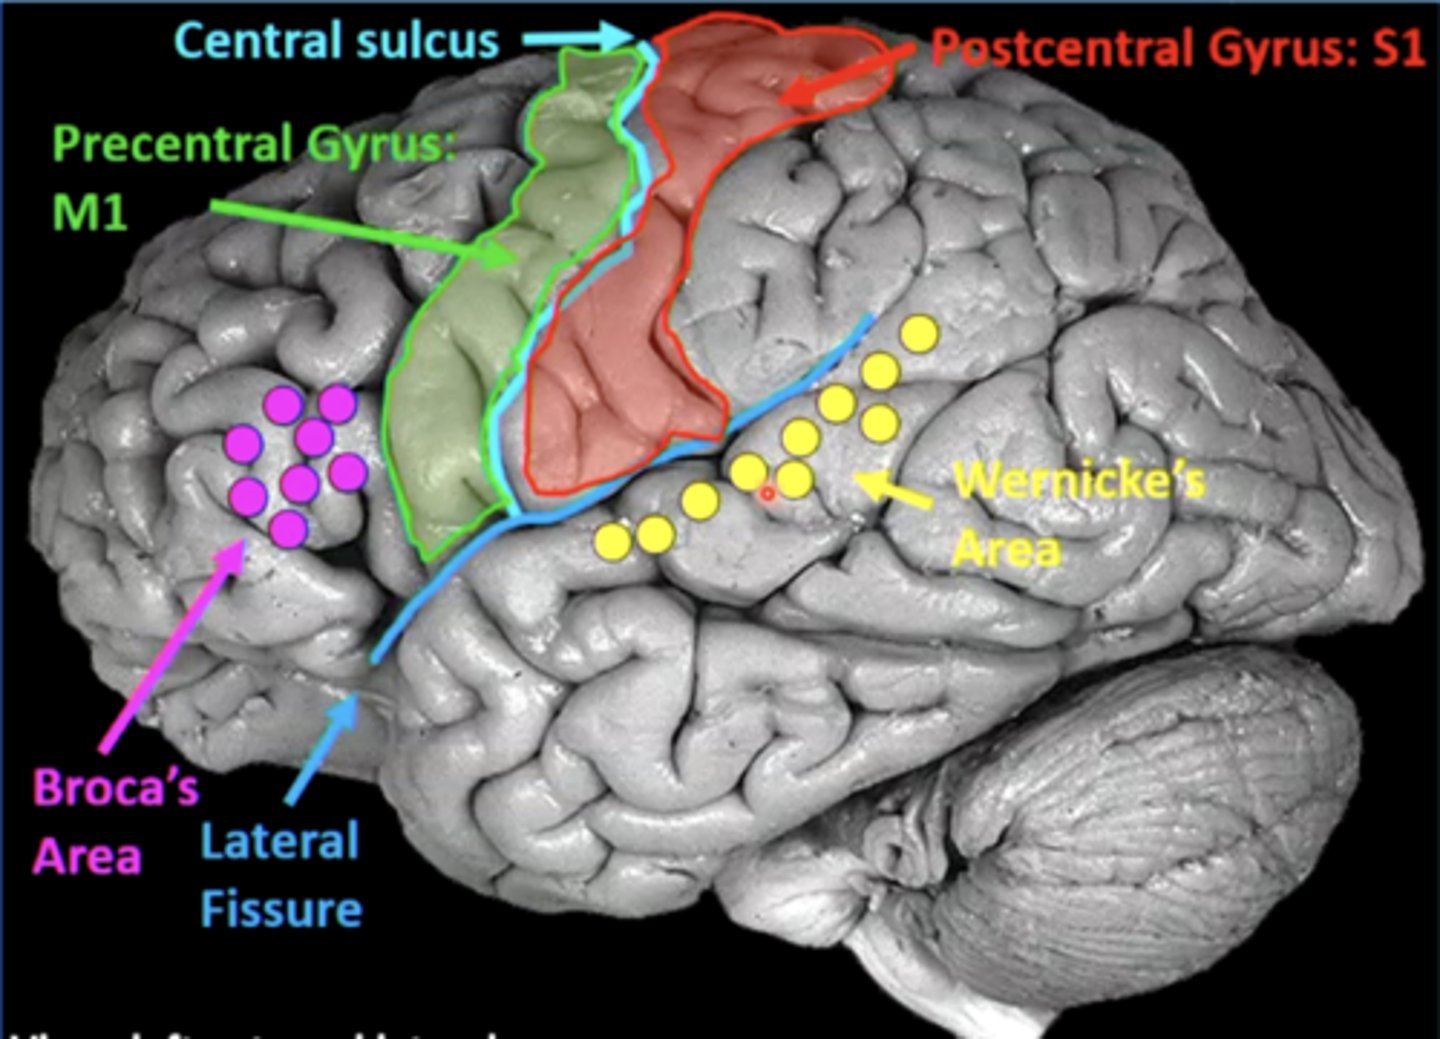

list the cortical region and cerebral lobe of the somatic motor system/primary motor cortex:

cortical region:

precentral gyrus

cerebral lobe: frontal (M1)

list the cortical region and cerebral lobe of the somatosensory system/primary sensory cortex:

cortical region:

postcentral gyrus

cerebral lobe: parietal (S1)

list the cortical region and cerebral lobe of the speech/language system:

cortical region:

Broca's and Wernicke's areas

cerebral lobe: frontal (Broca's) and temporal (Wernicke's)

Broca's and Wernicke's areas are located on the (left/right) hemisphere of the brain in most people

left

a good guess to where the language centers are is based on your dominant hand (right hand dominant --> language centers will be in the left hemisphere)

what is Broca's area?

area in the frontal lobe responsible for language production (speaking, writing, signing)

a lesion in Broca's area could result in what?

Broca's aphasia

results in slow, labored speech, agrammatism (lacking correct grammar), and anomia (inability to name objects)

understanding is good, finding/creating the words is difficult

what is Wernicke's area?

area in the temporal lobe responsible for language comprehension (speech, written language, sign language)

a lesion in Wernicke's area can result in what?

Wernicke's aphasia

person can produce fluent speech/language, but it is meaningless ("word salad")

language production is there, it just makes no sense

what is the arcuate fasciculus?

an axonal pathway that connects Wernicke's area to Broca's area

cell bodies are in Wernicke's area, and axons synapse in Broca's area